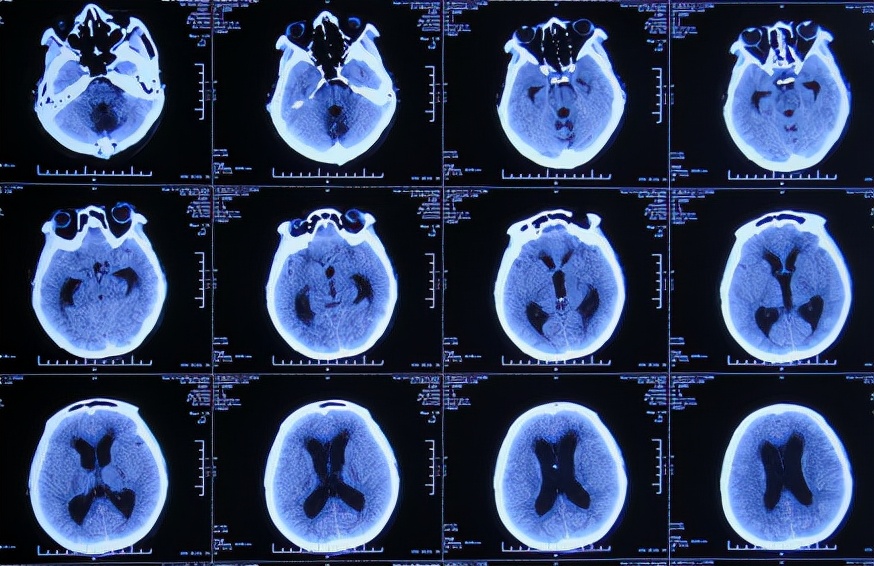

2019年6月21日(脑出血后113天)住入李小勇脑脊液科,入院时:精神差;头部、后颈、双肩疼痛;睡觉时有尿*禁失**;双侧眼皮不能闭合(不能眨眼)( 图-16 );走路差。当天查头颅CT示脑积水( 图-17 )。

图-17: 2019年6月21日头颅CT

入院治疗3天即2019年6月24日,进行了脑室腹壁外引流术,术后当天查头颅CT示脑室引流状态( 图-18 )。

图-18: 2019年6月24日头颅CT

入院治疗6天即2019年6月27日,查头颅CT示脑室缩小( 图-19 ),但有少量出血,当天给予脑室引流管调整术。

图-19: 2019年6月27日头颅CT

术后次日复查头颅CT示引流管位置良好( 图-20 )。

图-20: 2019年6月28日头颅CT

入院治疗10天即2019年7月1日,复查头颅CT示脑室缩小、出血基本消失( 图-21 )。

图-21: 2019年7月1日头颅CT

入院治疗17天即2019年7月8日,入院时不能眨眼已变基本正常,头部疼痛较入院时有减轻( 图-22 );查头颅CT示虽有少量硬膜下积液,但脑室基本正常( 图-23 )。

图-23: 2019年7月8日头颅CT

入院治疗53天即2019年8月13日,进行了脑室腹腔分流术( 图-24 )。

图-24: 2019年8月13日头颅CT